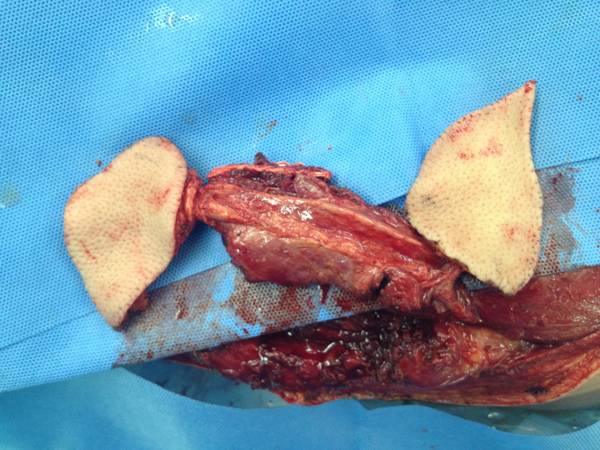

切取